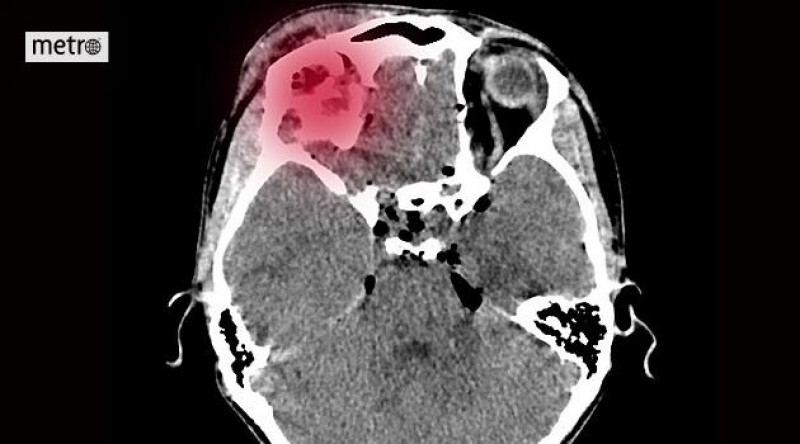

Do nemocnice přišel čtyři hodiny po mrtvici. Přerov má vlastní iktové centrum a šetří čas

Na prahu sedmdesátky ženě najednou znehybněla polovina těla, ochrnula na pravou ruku i nohu. Zavolala si záchranku a ta ji okamžitě převezla do přerovské nemocnice.